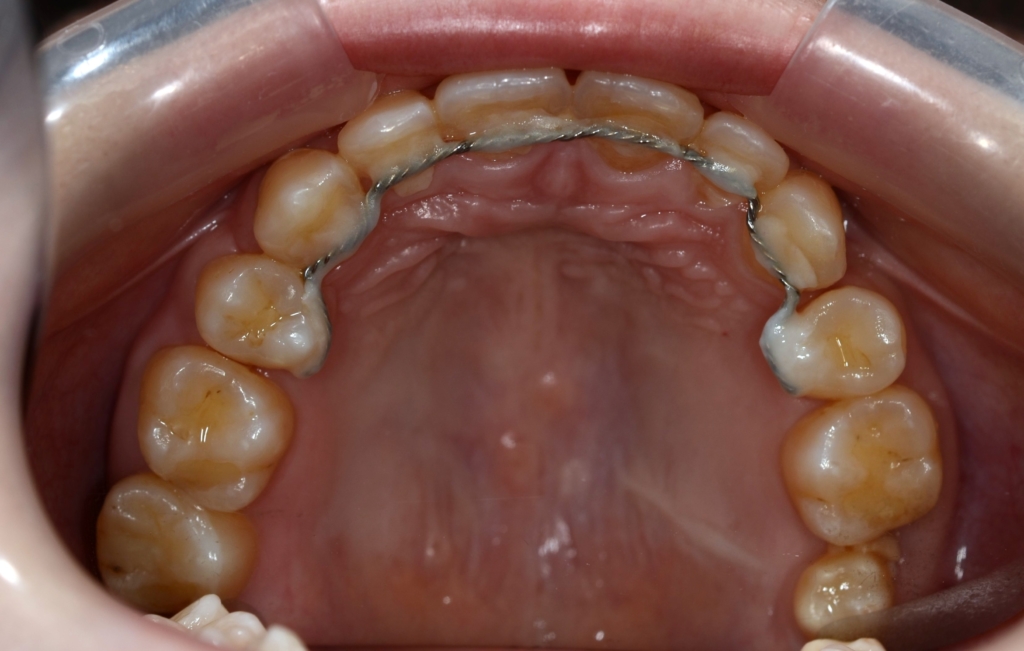

【保定】 上下ともフィックスタイプ&クリアリテーナー

ついでに、歯並びの比較です

上段が矯正治療前、下段が矯正治療後